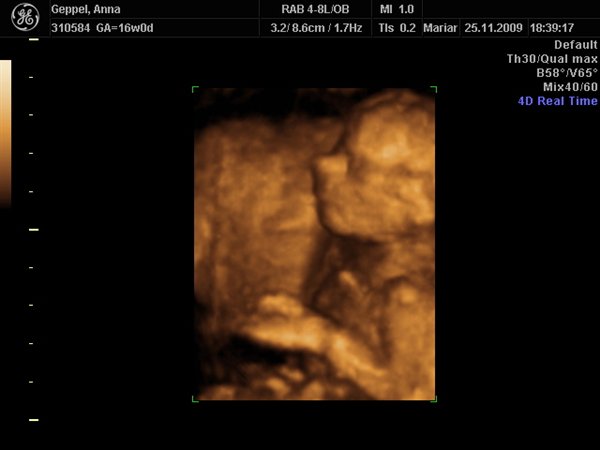

Det første var det bedste der blev taget i 3D, da det er svært at få gode 3D billeder allerede i uge 17! Synes han ser nuttet ud med sin lille opstoppernæse